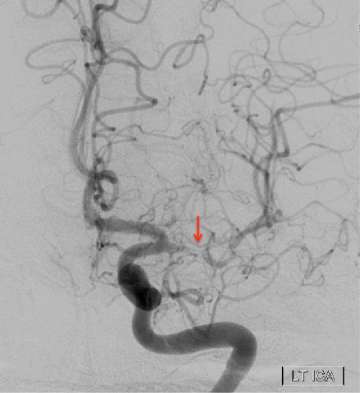

Moyamoya Figure 2

The figure shows multiple new arteries (arrows) growing from the scalp to the brain after an EDAS surgery in a patient with narrowing of the intracranial arteries. The arteries growing from the scalp resemble the tendrils of a vine reaching to supply additional blood to the brain.